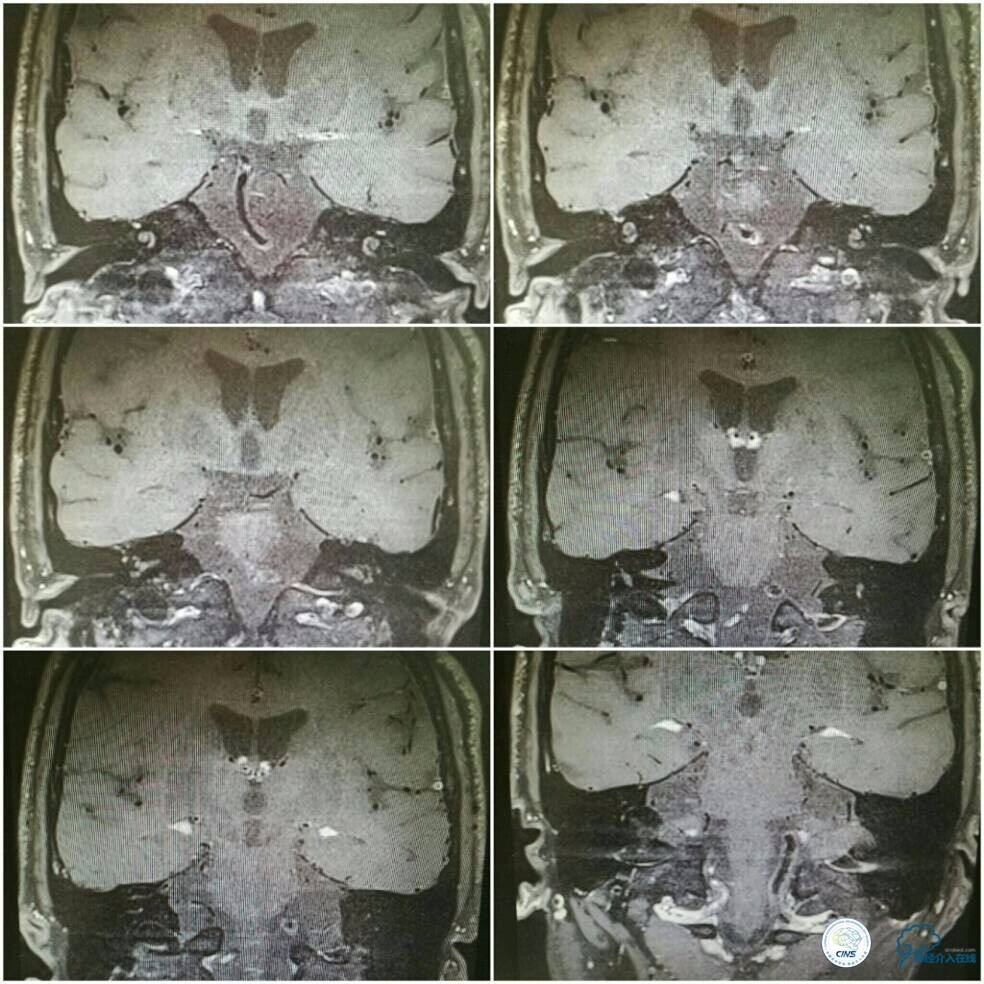

高分辨核磁提示左椎动脉V4段与基底动脉近段见偏心性斑块,偏下壁,伴环状强化;左椎动脉V4段病变处血管较近段正常血管相比,未见明显的管径变化; 右椎V4段闭塞,V3段内见血栓充盈(图7)。

图7